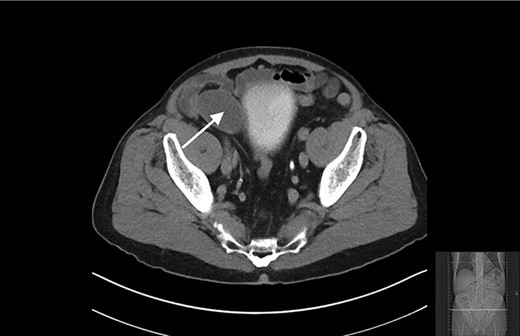

An 80-year-old gentleman was referred to General Surgery by the Urology department following an incidental finding on a computerized tomography (CT) urogram, performed for investigation of haematuria, which self-resolved. The finding was of a well-circumscribed hypodense mass in the right iliac fossa measuring 5.2 × 4 cm. There was subtle focus of calcification at its wall with no communication with the urinary bladder (Figs 1 and 2).

Transverse view of CT showing a well-circumscribed hypodense mass in the right iliac fossa.